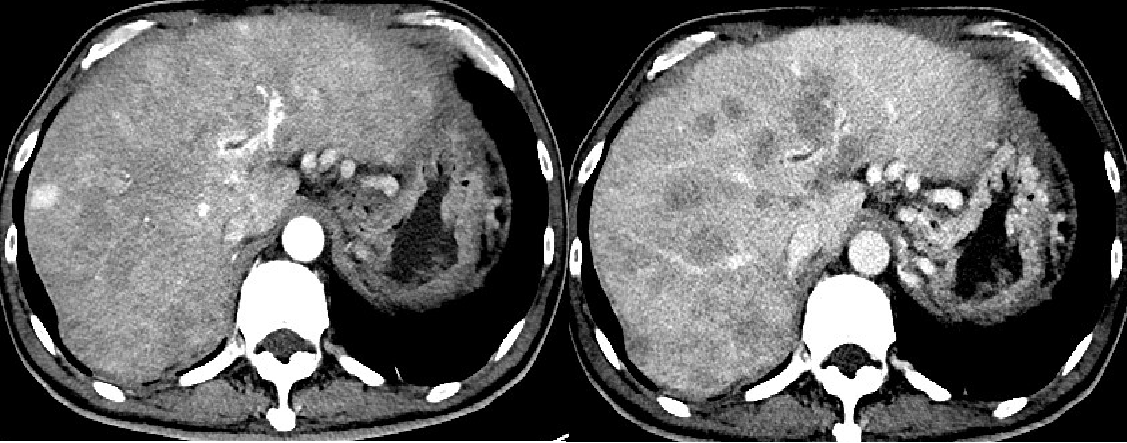

2019-5-28复查CT提示:

肝右叶部分缺失,残肝见多个结节低密度灶,边界欠清,增强扫描后轻度强化,考虑活性灶;门脉主干及左右支弥漫性增宽,可见充盈缺损,考虑癌栓。

2019-5-28: